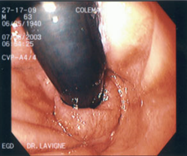

It is a clinical condition encountered in patients with general health problems, suppressed immune systems, or those who have used antibiotics for a long time. The most common cause of infectious esophagitis is Candida albicans.